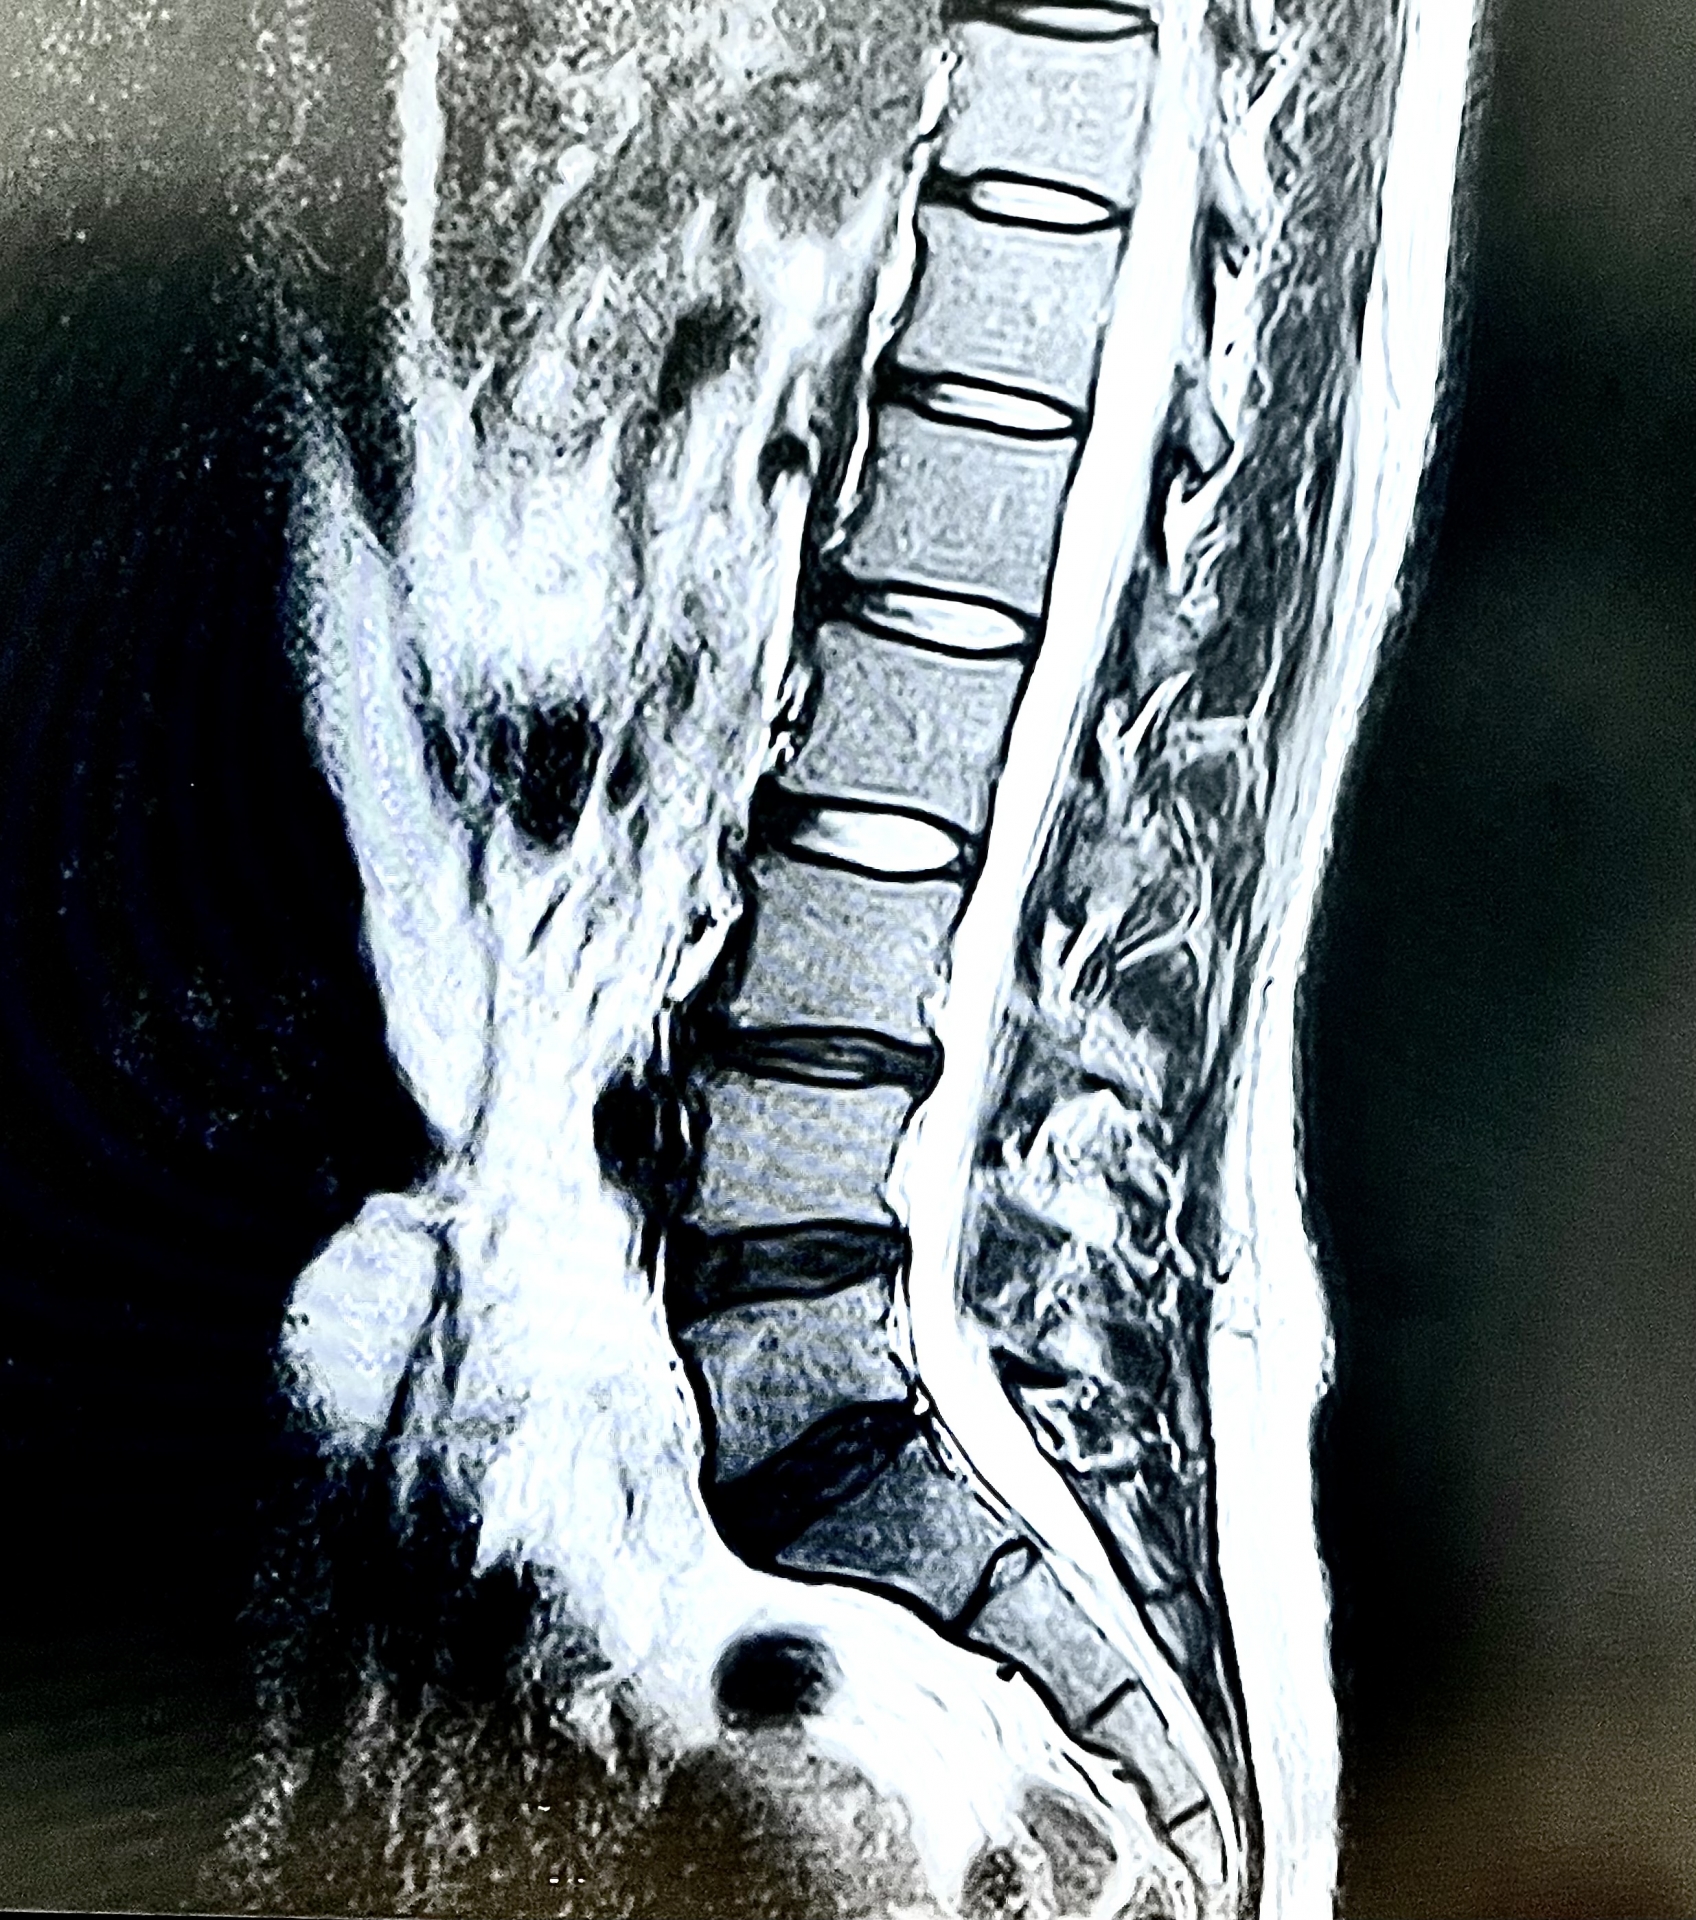

1. 的確な診断(レントゲン・MRI検査)

痛みの原因がどこにあるのかを画像検査で特定します。